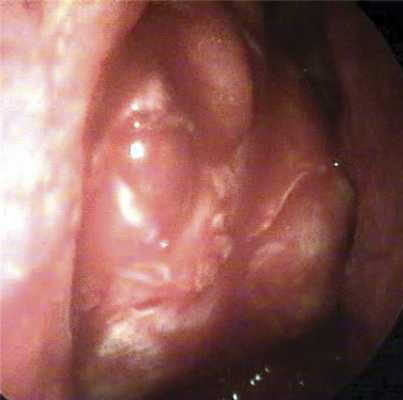

Далее серповидным ножом проводили вскрытие периорбиты. Разрезы выполняли в сагиттальной плоскости спереди назад. В зависимости от высоты костного окна накладывали от 2 до 4 сагиттальных разрезов. При этом для улучшения визуального контроля слегка надавливали на глаз, смещая его кзади и медиально. Дополнительно рассекались фиброзные перемычки между дольками орбитального жира, таким образом достигался максимальный пролапс орбитальных мягких тканей в костное окно (рис. 2). Орбитальный жир не резецировали.

Рис. 2. Эндофото результата эндоназального этапа костной декомпрессии орбиты: орбитальный жир пролабирует в сформированное окно.